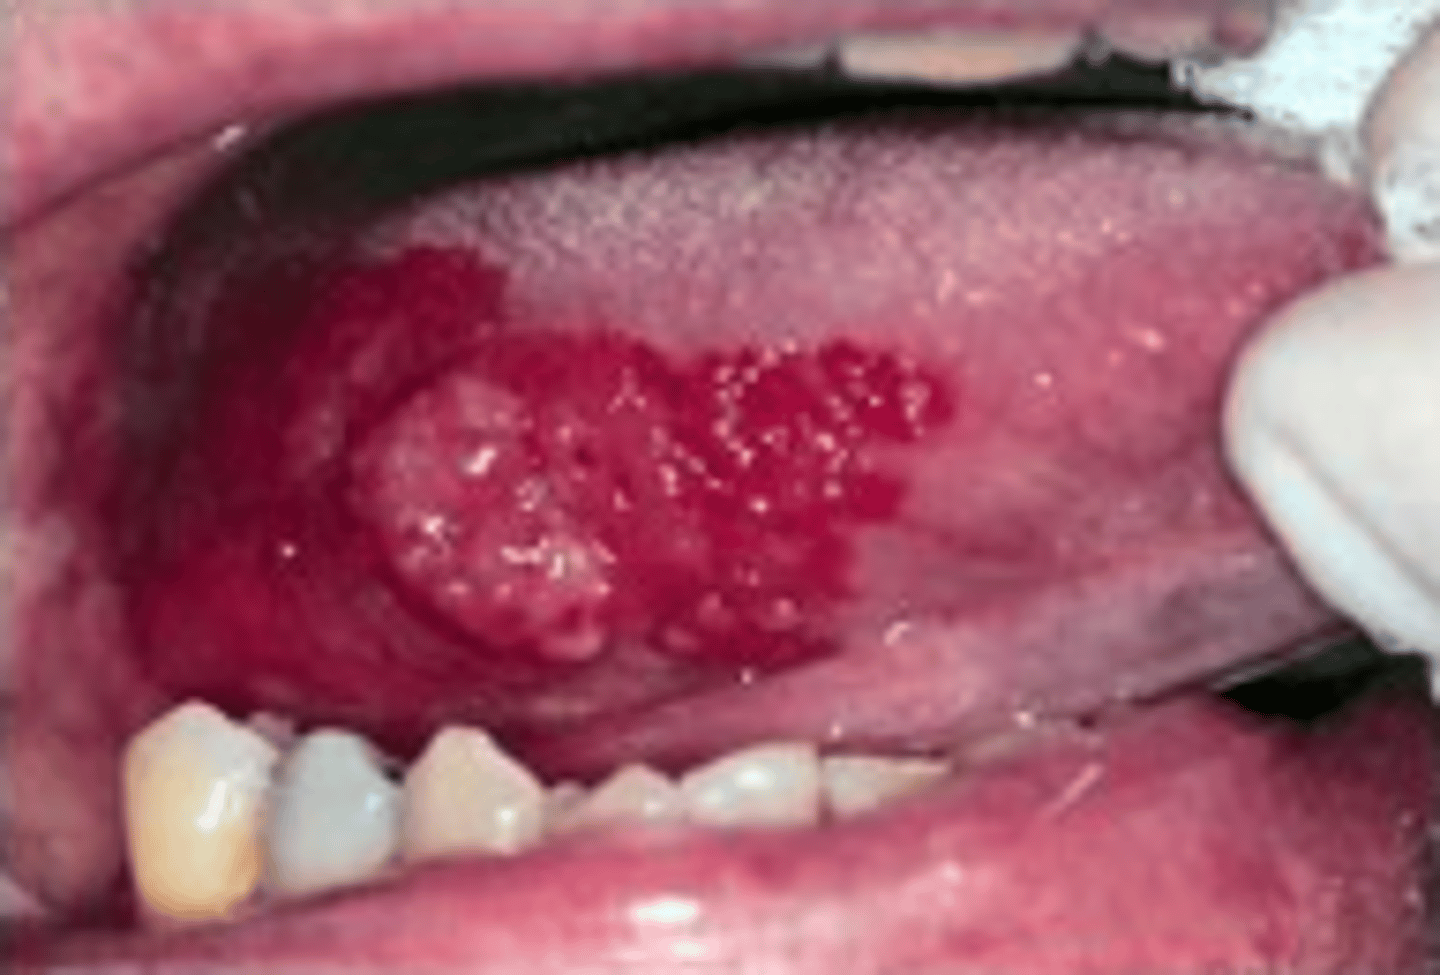

- erythematous/red velvety lesions present on R lateral border of tongue

- approx 5x3cm diameter & extends distally

- well circumscribed w/ an irregular margin

- exophytic/raised area centrally

Describe the appearance of the lesions:

A new patient attends for a replacement of restoration LR4, you notice a red patch on the side of the patient’s tongue which the patient was not aware of.

• 62 year old female

• CO: Nil

• RMH: Hypertension, had surgery for detached retina last year, diverticulitis

• SH: Non-smoker, alcohol 5-6 units/week

• RDH: Irregular attender

• EO: No lymphadenopathy, no asymmetry, no skin lesions, looks generally well

Case 4 background

How long has it been present for? Not sure as she wasn't really aware of it

When was the last time that she visited a dental professional? Many yrs ago

Is it painful? No

Does it bleed? No

Was she a past smoker or heavier drinker in the past? No

What questions would you ask the patient about the lesion?

Erythroplakia (potentially malignant lesion)

What is the likely diagnosis?

- urgent 2 week referral to OM/OS/O&MFS dept

NICE guidelines Dec 2021 state:

- consider an urgent referral for assessment for possible oral cancer by a dentist in ppl who have either:

> lump on lip or in OC or

> red/red & white patch in the OC consistent w/ erythroplakia or erythroleukoplakia

What would your management be?

referral necessary for an urgent biopsy to establish the diagnosis & further management as necessary

Would you refer the patient and if so why?

- imp pt understands they need an urgent referral so that a diagnosis can be made (until then oral cancer cannot be excluded)

- pt should be advised to attend her 2 week referral appt & delay her holiday otherwise the diagnosis & tx will be delayed & this could affect her prognosis

The patient is planning to go on holiday next week to her second home in Spain for a couple of months (post COVID era) and asks if she will still be ok to go?